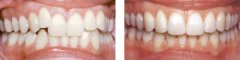

孩子牙齿拥挤可以做隐形矫正吗?

随着生活条件提高,食物越来越精细化,孩子的牙齿就会因为缺乏应有的锻炼,...【详细】

儿童牙齿拥挤问题严重吗?

经常接到类似的咨询,说孩子前牙比较不齐,应该属于拥挤那一类的,请问这种...【详细】